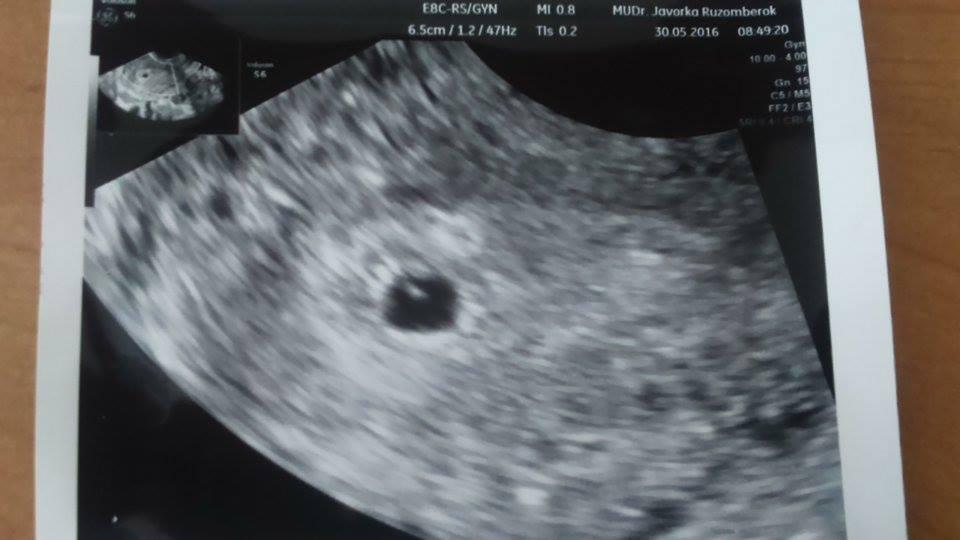

@mia295 jejoooo, krasna fotecka.Mna caka kontrola zajtra. Co to znamena pre tehu cysta? To by si musela byt celych 9 mes na PN? uvidis, zmizne ti.verim tomu 🙂Aka mala zlata fazulka. Muz ta už obskakuje ako moj? aj ti je blbo? Moj chlap v sobotu vysaval a mopoval.No riadne som sa na nom smiala,aky bol spoteny. Ale musim uznat,ze si to o to viac vazil a daval pozor na omrvinky 🙂

@petulik1991 Moje drobatko je o nieco mensie ako tvoje,takze ja som cca týžden dozadu. Vo stvrtok by som mala byt 8+0,tak uvidime ci to podla velkosti tak bude sediet.Hlavne nech rastie a nech bije srdiecko. Jasne, ze dam vediet. Dnes ideme opekat do lesa s kamosmi,tak som zvedava ako to zvladnem 🙂

@tinka881 No vidis, tak nakoniec si predsa mala tu ovulku neskor 🙂) Nas susnik mal namiesto ocakavanych 8+0tt takmer 8+4tt 😀 Drzim palceky, aby mal co najviac 🙂 Ale hlavne aby srdienko bilo. Ja mam dalsi utz niekedy v polke juna, to uz by sa mal v brusku pekne mrvit, tak sa tesim. To je nieco ako srdiecko na zaciatku a potom su to tanecky na utz 😎